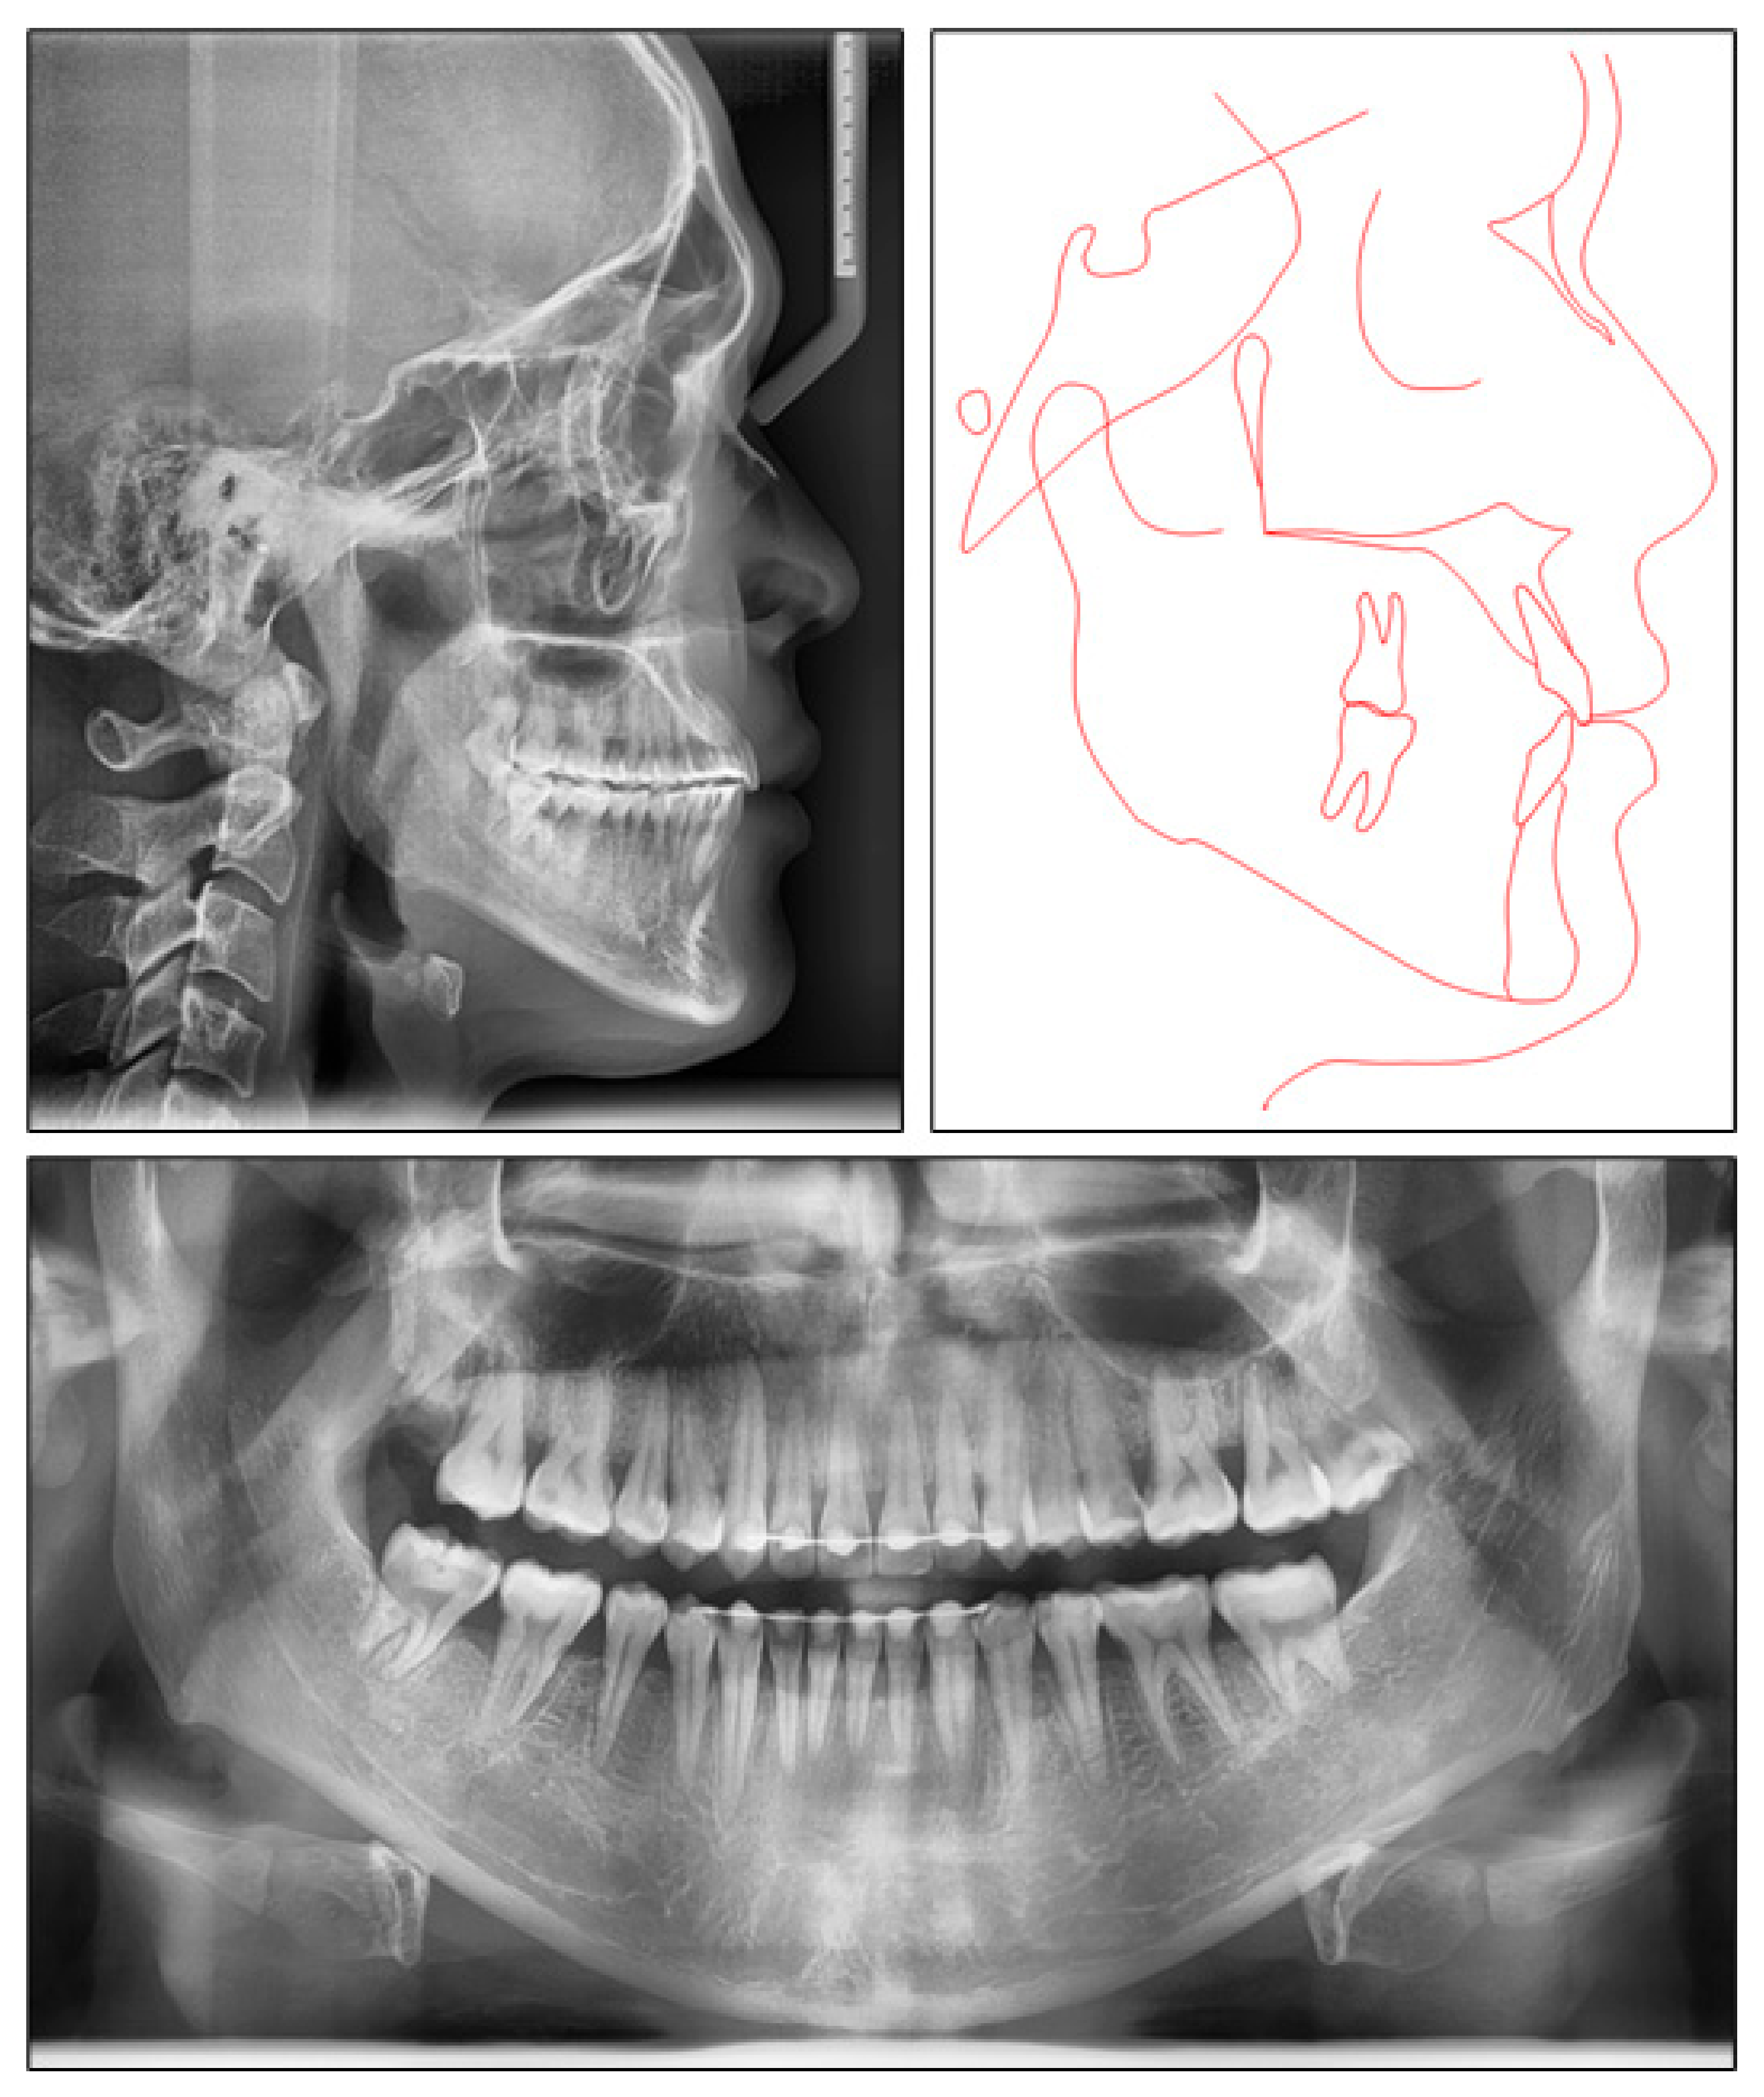

Figure 3.

Pretreatment radiographs and tracing.

The panoramic radiograph indicated that four third molars were present, upper right third molar was hopeless and lower right third molar was mesially tipped. The lateral cephalometric analysis showed a skeletal Class III jaw relationship with mandibular protrusion (ANB, −2.1°; Wits appraisal, −8.1 mm; SNB, 87°), and hyperdivergent facial pattern (FMA, 29°). The dental compensation could be seen with upper incisor proclination (U1-SN, 112°) and lower incisor retroclination (L1-MP, 77.2°). Both the upper and lower lips were behind the E-line (Figure 3).